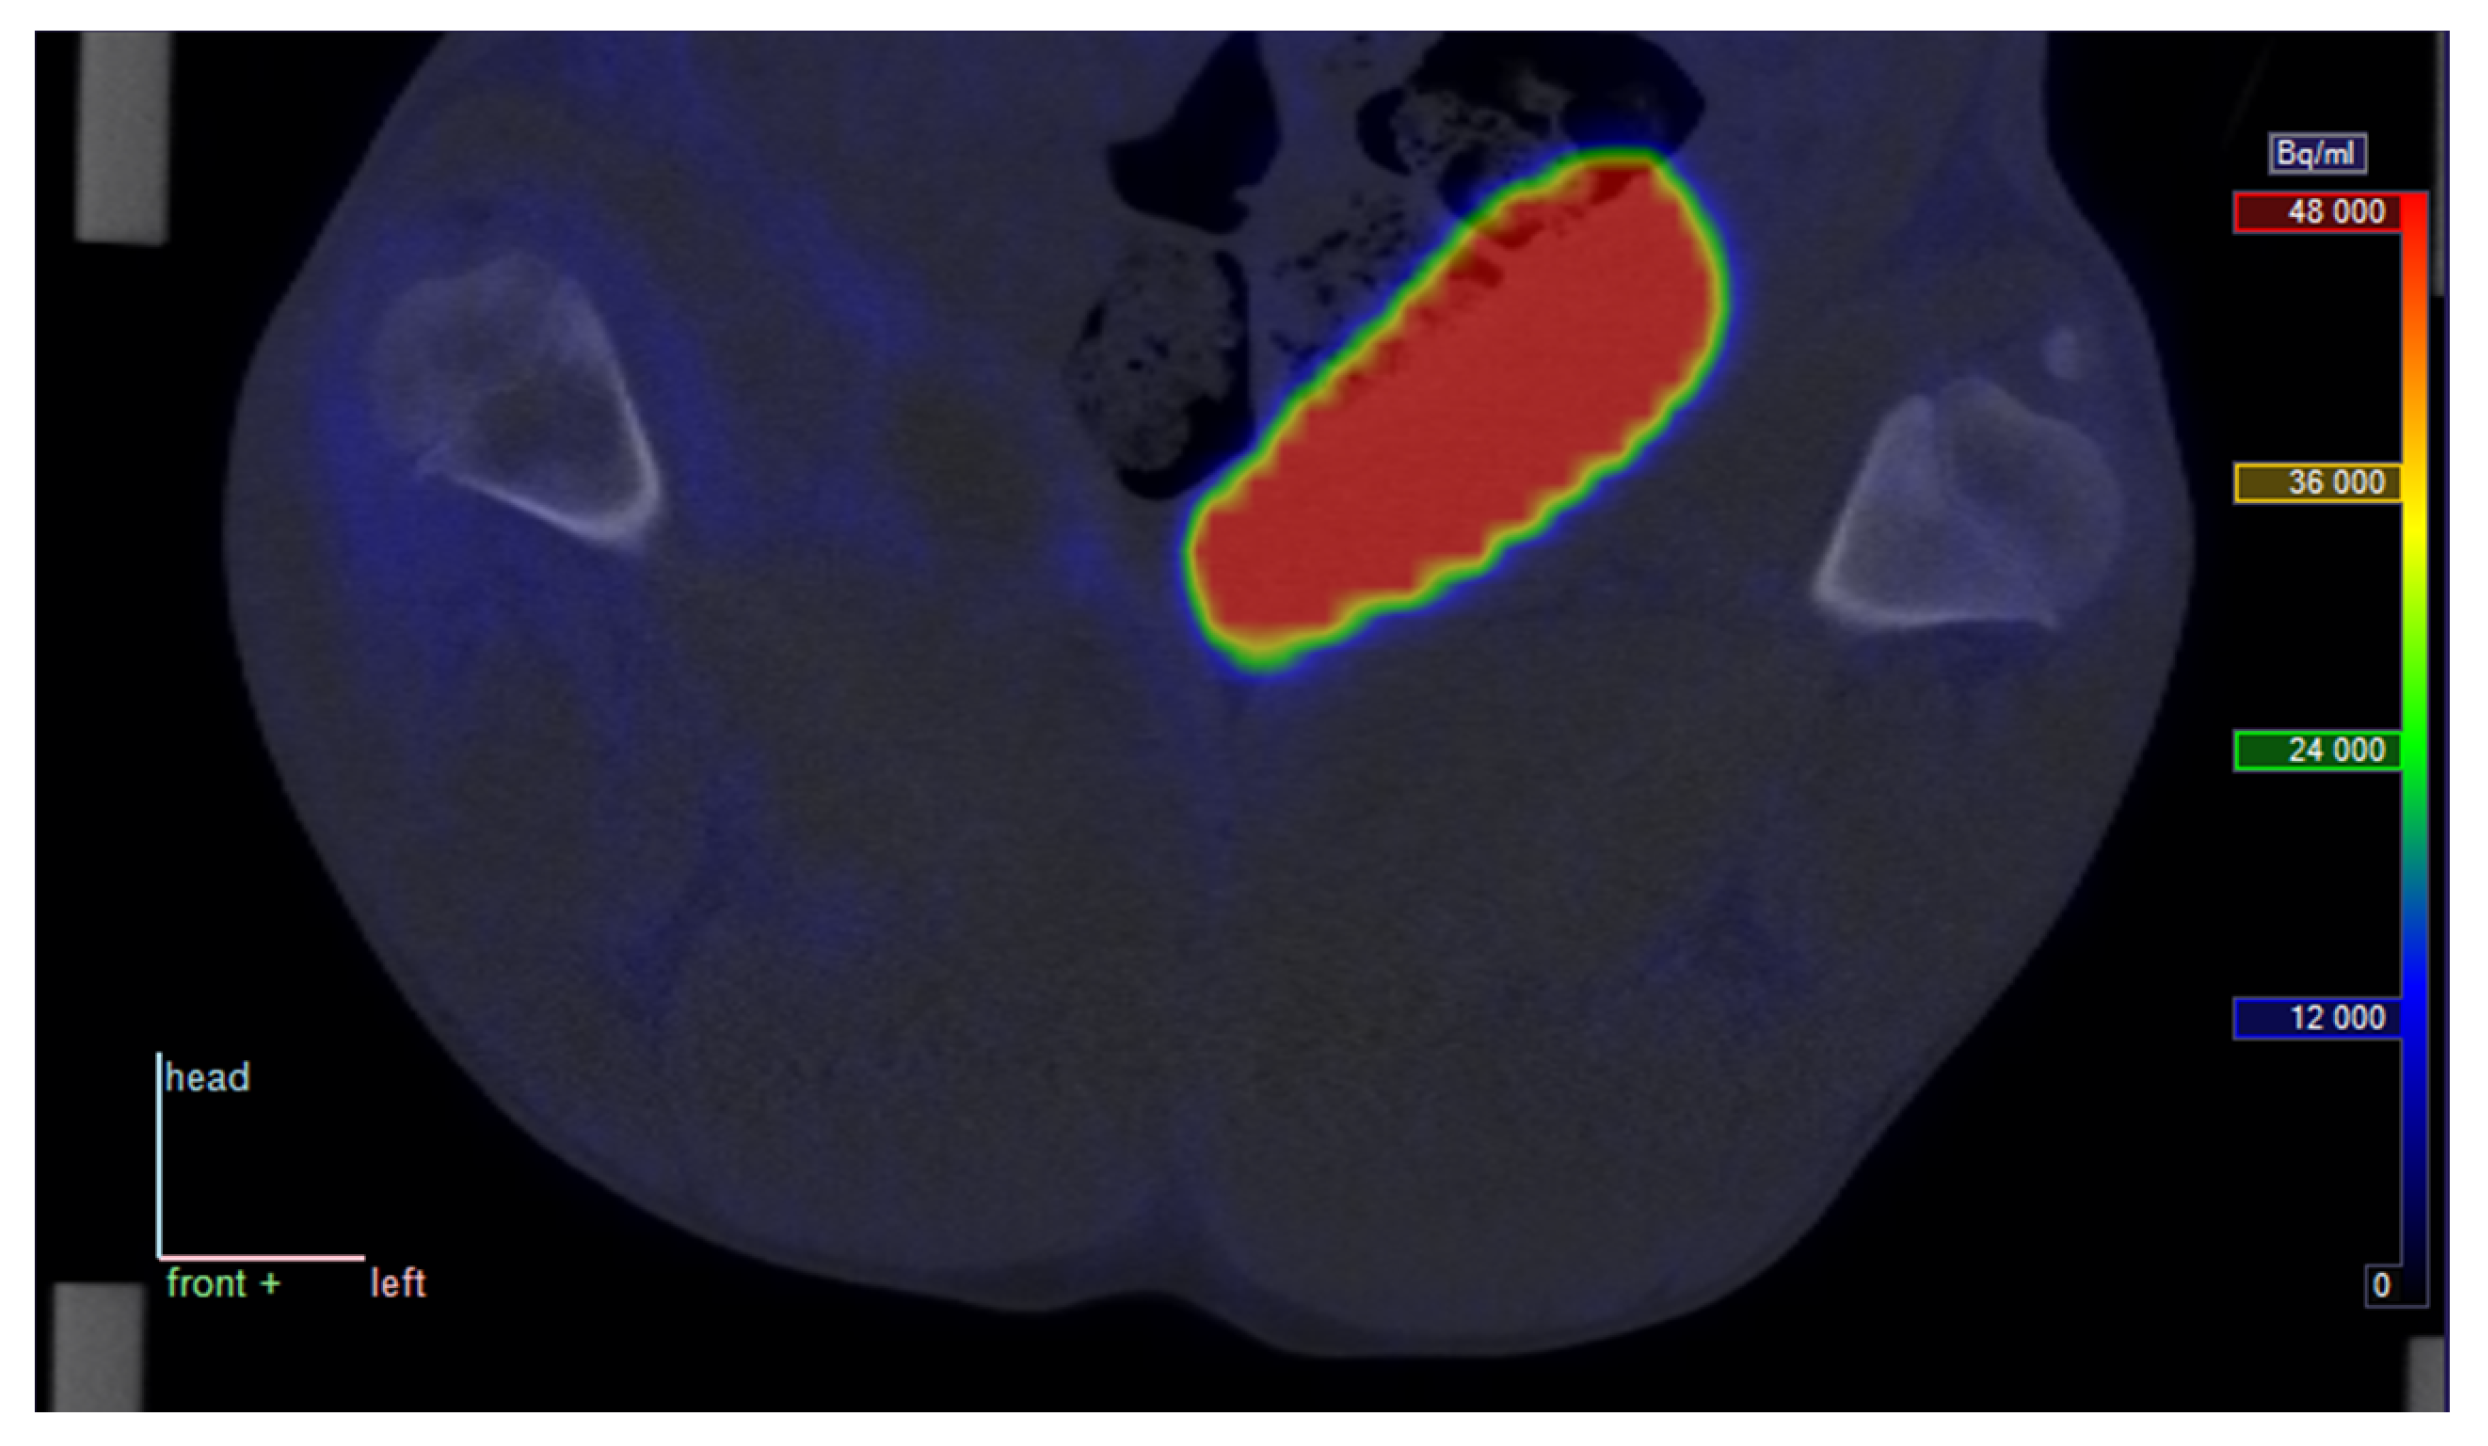

2.1. Visual Uptake

Visually, [68Ga]Ga-DOTA-Siglec-9 showed elevated uptake in inflamed and infected soft tissues, while not being prominent in infected bone (osteomyelitis). As an example, a coronal view of the uptake around the femur in pig no. 25 is shown in Figure 1.

In summary, [68Ga]Ga-DOTA-Siglec-9 shows increased uptake in infected (and inflamed) soft tissue compared with control tissue; however, this study fails to demonstrate elevated uptake in infected bone (osteomyelitis). These quantitative results correspond to the visual impression of the sample image in Figure 1, where increased uptake is clear in infected soft tissue but not in the infected bone (cf. with pig no. 25 in Table 2 and Table 3). Note, however, that this comparison is partly qualitative. The determination of VT on a reliable absolute scale will depend on improved knowledge on the nature of the radioactive metabolite products of [68Ga]Ga-DOTA-Siglec-9. The moderate correlation between SUV and VT indicates that the volume of distribution gives information that is not just a complicated version of the SUV.

Figure 1. Representative PET/CT image from pig no. 25. The pig was lying supine with roughly upward-pointing limbs, and the view is coronal, seen from the ventral side of the animal (“front” = opposite of back is in the direction of the reader); the top of the image is in the direction of the animal’s head. Full arrow: Uptake in phlegmon/early abscess at the right distal femur. Dotted arrow: Similar non-infected tissue for comparison. Red circles show sections of volumes of interest (VOIs) in soft tissue, black ellipse/circle show VOIs in bone tissue. The PET image represents the summed data from 15 to 30 min post-injection (p.i.). The tissue samples presented in Figure 3 were taken from positions approximately corresponding to the soft tissue VOIs.